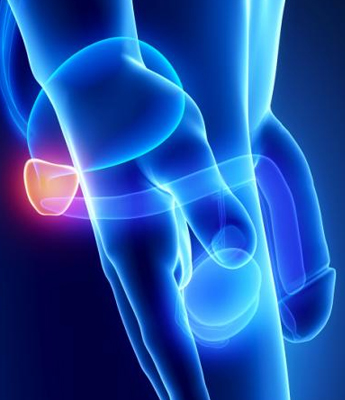

The prostate gland is a small, walnut-sized exocrine gland located at the base of the bladder. It plays a vital role in the male reproductive system by producing a significant portion of semen and providing nourishment to sperm, essential for their transport and protection during ejaculation. Disorders of the prostate, which are common in men over the age of 45, can significantly impact prostate function and overall health. Conditions such as Benign Prostatic Hyperplasia (BPH) cause the prostate to enlarge and may lead to urinary difficulties, while Prostatitis, an inflammation often resulting from infections or other causes, can produce symptoms like pelvic pain and urinary discomfort.

Prostate Cancer, a serious condition involving the development of cancerous cells in the prostate, is another critical concern. Regular consultations with a urologist are crucial for maintaining prostate health. Urologists provide valuable screenings, expert advice, and tailored treatment recommendations to address prostate disorders effectively. Early detection and management of these conditions are essential for preserving quality of life and ensuring optimal prostate function.